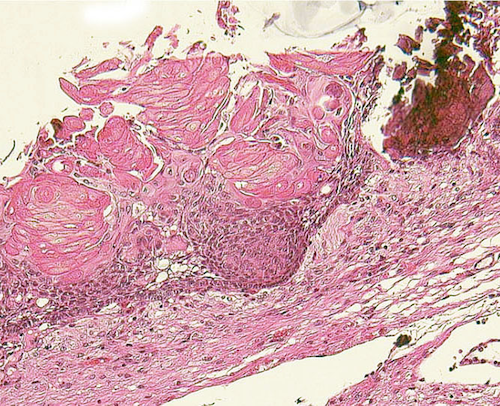

adamantinomatous type(ほとんどこのタイプ)

エナメル上皮腫型といいます。組織学的にはwet keratinを含むことが特徴で,この所見でpapillary typeと区別ができます。基底層が一列に配列し,それに続いて上皮細胞があり,一部に疎な結合職と小血管の部分,石灰化,小のう胞が存在します。のう胞内容液は,肉眼的に暗緑褐色でmachinery oilと表現される。脳組織(特に視床下部)に浸潤し,神経や血管に癒着します。まれに石灰化ではなく,真の骨化がみられる。

Scarce squamous epithelium with basal vascular network of cyst wall

Craniopharyngioma with wet keratin structures (upper left) and calcification (upper right).